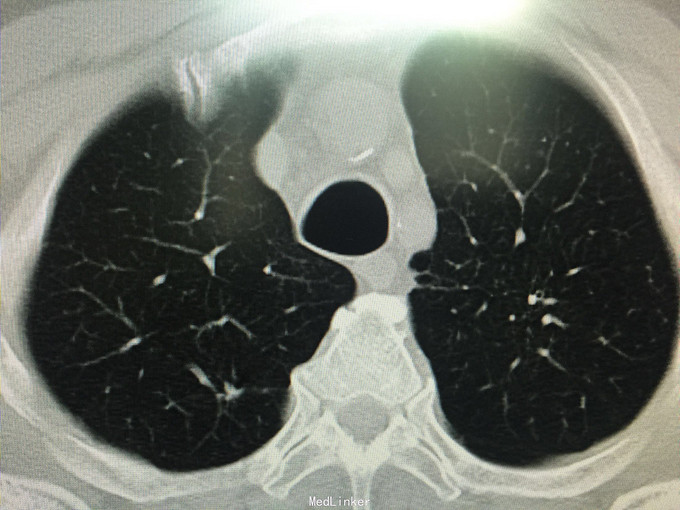

男性,70岁, 主诉:发现左肺上叶占位12个月 现病史:2014.10月患者出现胸背部疼痛不适,对症理疗未见好转。2014.11月出现咳嗽,咳痰带血丝,行胸部CT检查示:左肺上叶占位病变,恶性可能性大。2014.11.13患者行PET/CT检查提示:左肺上叶软组织密度肿块影伴周围片状密度增高影,代谢增高,考虑恶性病变伴周围炎性改变。纵隔内及左肺门多发淋巴结影,代谢增高,考虑为恶性病变转移。左肾上腺结节,代谢增高,考虑为恶性病变转移。第2胸椎棘突骨质破坏,代谢增高,考虑为恶性病变转移。肿瘤标志物:CA125 625 U/ml。因肿块位置较高,未行纤维支气管镜取病理,患者因年龄大,拒绝行肺肿物穿刺活检,故病理不明确。但根据肿瘤影像学形态及理化检测,怀疑为腺癌,建议患者行TKI靶向治疗,同时给予双磷酸盐治疗骨转移。患者口服TKI一个月后复查胸部CT肿块明显缩小,胸背部疼痛消失。患者现口服TKI约11个月,无明显咳嗽咳痰,无背部疼痛。近1周,患者诉偶尔咯鲜红色粘痰,伴有咽部及胸前区闷痛疼痛无明显咳嗽症状,为求复查而来诊。复查胸部CT较之前对比未见明显变化。复查肿瘤标志物:CEA、CA-125、NSE均未见异常。

查体:BP 165/75mmHg,双肺呼吸引清,未闻及干湿罗音,心音钝,心律齐,心率72次/分,各听诊区未闻及杂音。腹平,未见胃肠型及蠕动波,腹软,全腹无压痛,无反跳痛及肌紧张,肝脾肋下未触及,墨菲氏征(-),移动性肝肾区无叩痛,移动性浊音(-),肠鸣音4次/分。 辅助检查:肝胆脾彩超:未见明显异常。 胸部CT:较2015.8月对比未见异常,左肺上叶陈旧性改变。 肿瘤系列:CEA、CA-125、NSE均未见异常。